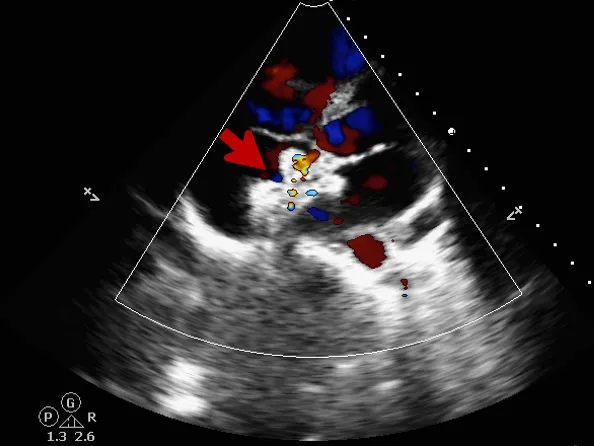

锁定后评估

心尖四腔心切面可见封堵器形态良好

主动脉短轴切面可见封堵器呈“Y”字型抱住主动脉

彩色多普勒血流成像显示无残余分流存在

释放后评估

封堵器位置正确、形态良好

封堵成功